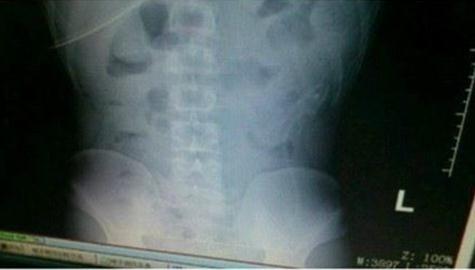

英国《都市报》报道,中国广东顺德一名39岁男子日前模仿色情电影镜头,把一条活鳗鱼塞进屁股,结果拔不出来了。他赶忙到附近医院救治,医生花了数个小时,才取出鳗鱼。鳗鱼被取出还活着,但很快就死了。当地警方称,他们将对该男子展开虐待动物调查。